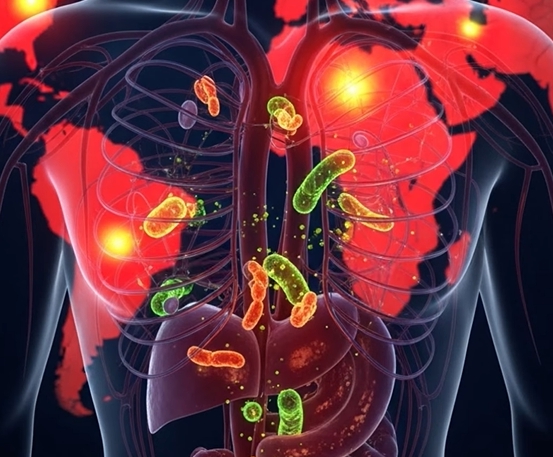

패혈증은 대부분 특정 부위 감염이 혈액을 통해 전신으로 퍼지면서 발생합니다. 감염 자체보다 면역계가 과도하게 반응하는 것이 핵심 원리입니다. 대표적인 원인은 다음과 같습니다.

- 호흡기 감염 → 폐렴, 기관지염, 폐농양 (가장 흔한 원인)

- 요로 감염 → 방광염, 신우신염

- 복부 감염 → 충수염, 담낭염, 복막염

- 피부 및 연조직 감염 → 상처 감염, 봉와직염

- 수술 후 감염, 의료기기 감염(카테터, 인공관절 등)

- 면역 저하 환자의 기회감염

세균 독소와 염증 물질이 혈관 내피를 손상시키면서 혈압 저하와 장기 손상이 발생합니다.